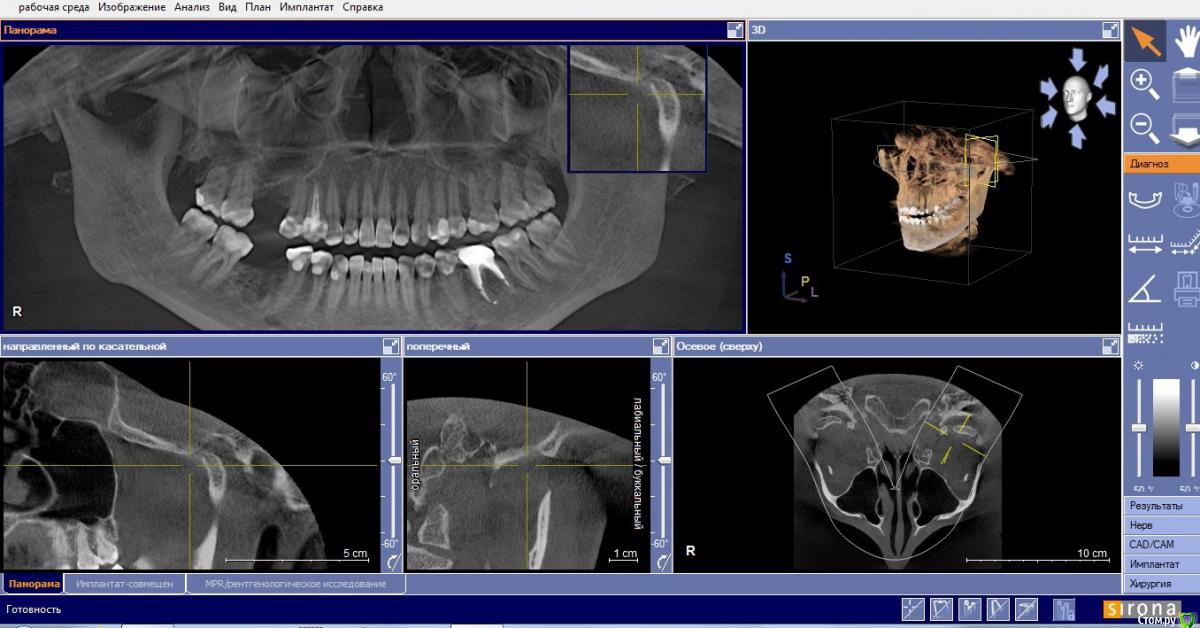

Маргарита19 Опубликовано 22 августа, 2016 Автор Поделиться Опубликовано 22 августа, 2016 Уважаемые стоматологи, помогите, пожалуйста определиться с выбором импланта и схемы лечения. вопрос идет только о 46 зубе, на синус-лифтинг пока не могу решиться. Посетив несколько клиник, стою перед выбором из 2 вариантов: 1. Имплант Нобель Коникал коннекшн (8 мм), временные коронки, потом циркониевые коронки. Но здесь есть еще нюанс, ортодонт советует установить брекеты на нижнюю челюсть, чтобы выровнять передние зубы, там есть небольшая скученность. Сначала подпилить зубы немного по ширине, а потом приклеить брекеты только на 8 зубов, т.к. клыки смыкаются четко. Пока ТРГ и слепков нет, это предварительный план. Меня никогда не беспокоили нижние зубы в плане кривизны. Но, как я поняла, есть нездоровая стираемость зубов. 2. Хирургический шаблон, подсыпать кость искусственную, и Имплант Биотек Коннект (12мм), потом коронки МК, без временных. Про истираемость зубов ничего не сказали, но я и не спрашивала, если честно. Знакомых или проверенных врачей или клиник нет у меня. Вот пытаюсь понять в чьи руки отдаться. Ибо через пол годика хочу решиться на синус и делать его уже имея опыт общения с докторами. Какая схема на ваш взгляд более логичная и какой имлант лучше поставить? Заранее благодарю. Снимки прикрепляю как смогла сделать с КТ. Ссылка на комментарий

Bier Опубликовано 22 августа, 2016 Поделиться Опубликовано 22 августа, 2016 я бы поставил имплантат длиной 8-10мм + подсадка слизистой. По поводу брекетов - имплантата они в данном случае не касаются, это отдельная проблема. 1 Ссылка на комментарий

Маргарита19 Опубликовано 22 августа, 2016 Автор Поделиться Опубликовано 22 августа, 2016 я бы поставил имплантат длиной 8-10мм + подсадка слизистой. По поводу брекетов - имплантата они в данном случае не касаются, это отдельная проблема.Спасибо! А почему не 12?, чтобы не подсыпать кость? Ссылка на комментарий

Bier Опубликовано 23 августа, 2016 Поделиться Опубликовано 23 августа, 2016 Нет, просто в этом нет никакого смысла 1 Ссылка на комментарий

Маргарита19 Опубликовано 23 августа, 2016 Автор Поделиться Опубликовано 23 августа, 2016 Нет, просто в этом нет никакого смыслаИзвините, нет смысла в длинном импланте или в дополнит кости? Ссылка на комментарий

Доктор Хаус Опубликовано 23 августа, 2016 Поделиться Опубликовано 23 августа, 2016 Нету смысла в длинном имплантате 8-10 мм отлично передают жевательную нагрузку в кость . А вот в толстой десне окружающей место соединение имплантат абатмент есть . Чем десна толще тем будет лутще . http://s61.radikal.ru/i174/1608/36/ac44455ad8ae.jpg Даже если не хватает чуть чуть кости , то её отсутствие можно компенсировать подсадкой Десны . Это сейчас очень модно. Надежно . И для вас это будет легче. Вот примерно так..http://s012.radikal.ru/i319/1608/5e/86488fd41c8e.png Ссылка на комментарий